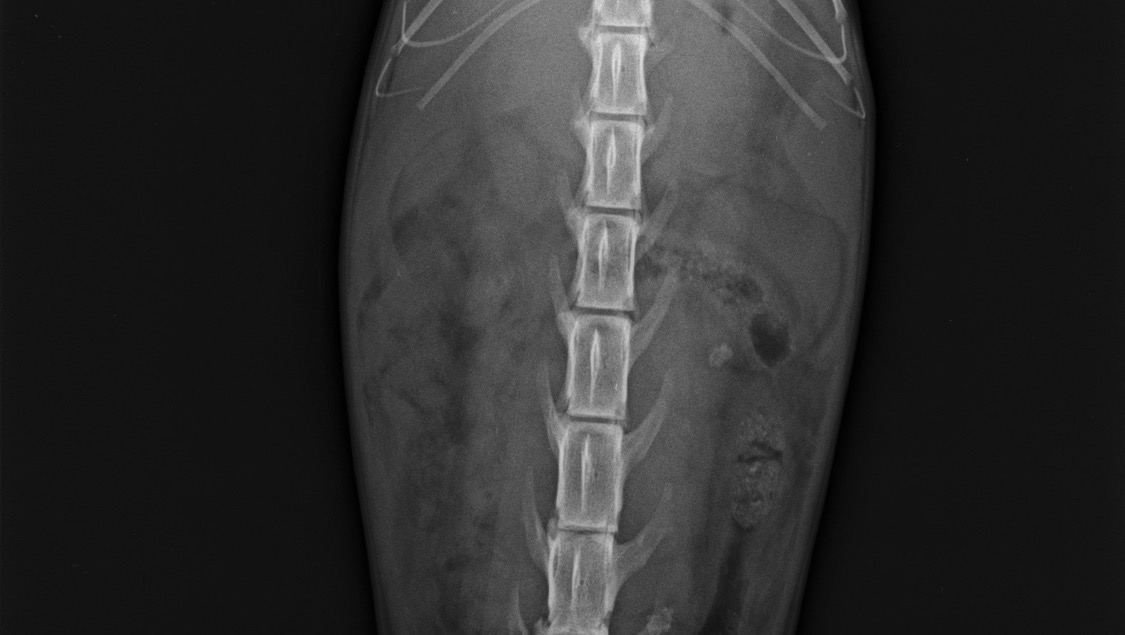

El veterinario que lo atendió sospechaba entre un cuerpo extraño y PIF, debido a que encontraron líquido libre en su radiografía. Le realizaron una cirugía exploratoria, en la cual se descartó presencia de cuerpo extraño, intususcepción y masa abdominal, quedando viva la sospecha de Peritonitis Infecciosa Felina (PIF), una enfermedad muy agresiva, que basta realizar una búsqueda en google para alarmarse.